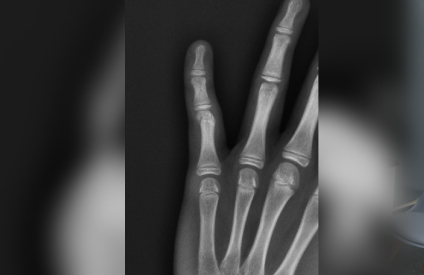

Our digital X-ray services are essential for diagnosing various orthopaedic conditions, monitoring healing progress, and planning treatments. We use this technology for fracture detection, joint assessments, and pre-operative planning, ensuring precise and effective care for our patients.